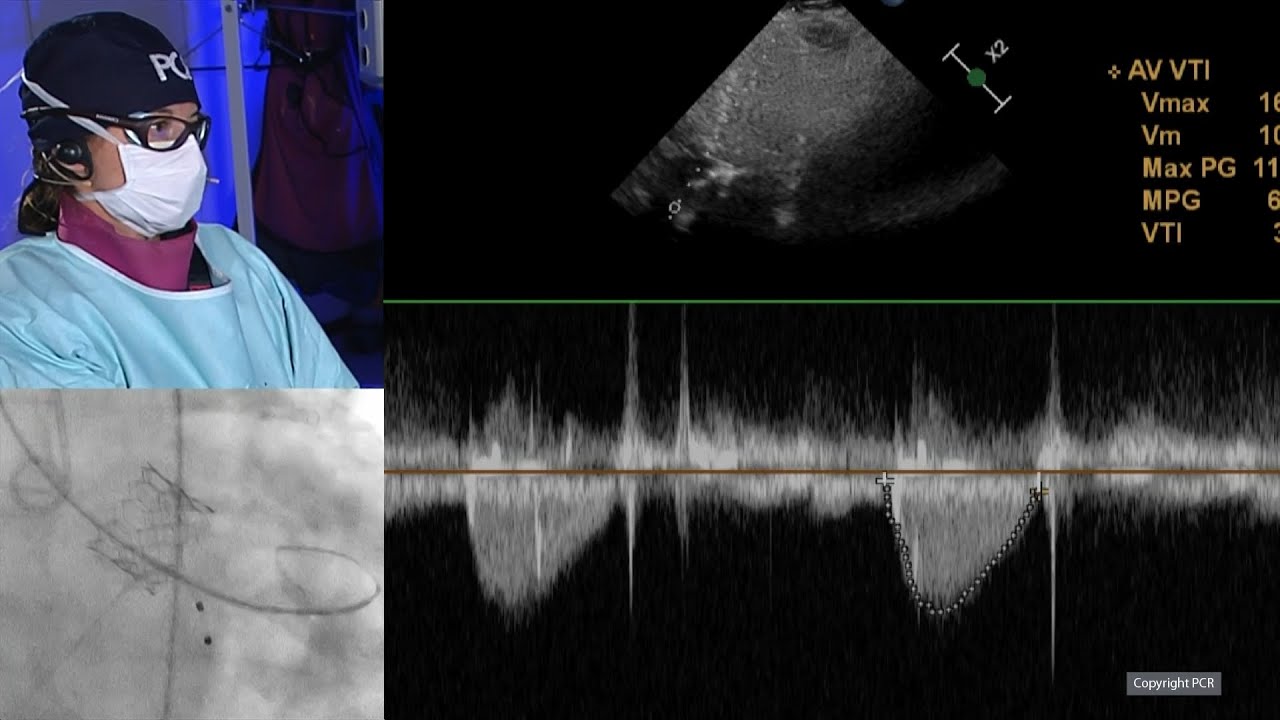

TAVI for bioprosthetic valve failure: LIVE Educational Case from Institut Cardiovasculaire Paris Sud - Massy, France